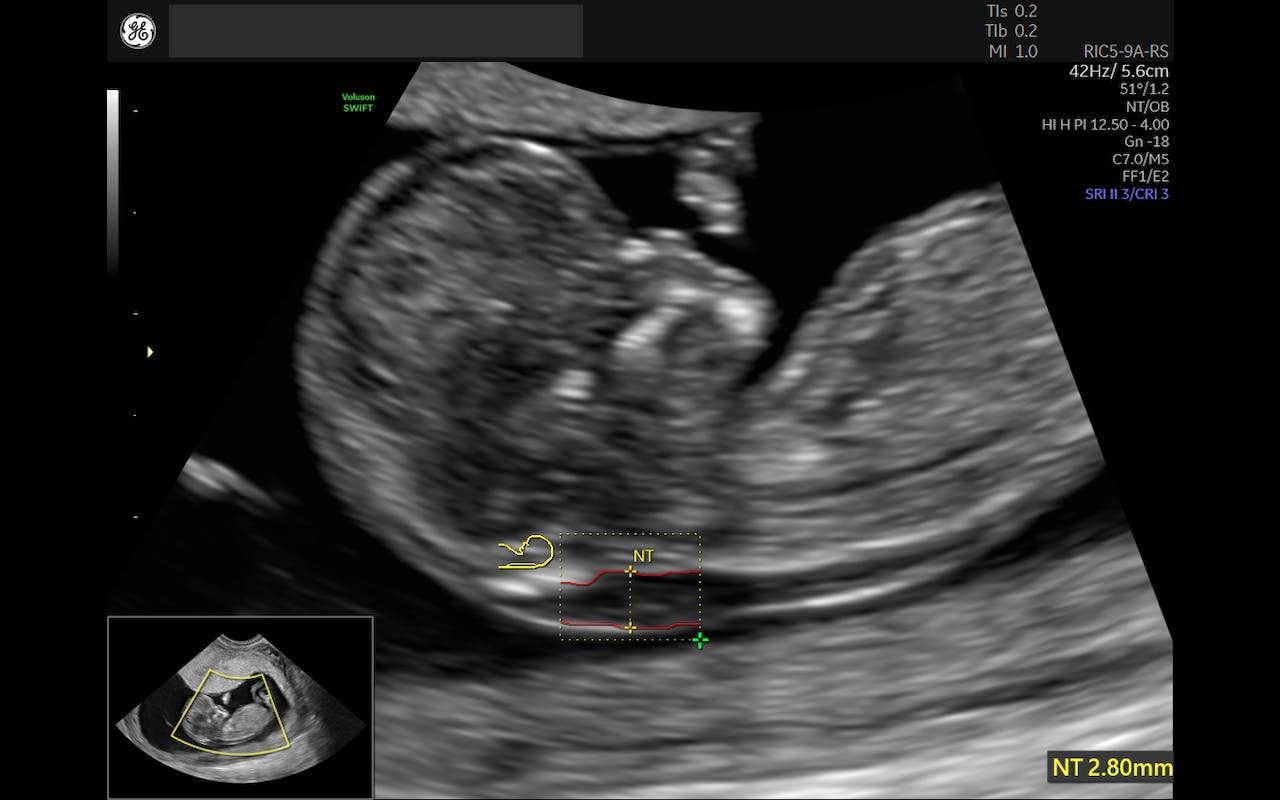

Trisomy 21 Screening Risk Assessment in the First Trimester

From volusonclub.net

Trisomy 21 Screening Risk Assessment in the First Trimester What Is High Risk Trisomy 21 Down syndrome (trisomy 21) is the most commonly recognized genetic cause of mental retardation. Down syndrome (trisomy 21) is a genetic disorder. Down syndrome is a genetic disorder caused when abnormal cell division results in extra genetic material from chromosome 21. Since chromosomes normally come in pairs, this is often referred to. What is trisomy 21 (down syndrome)? The risk. What Is High Risk Trisomy 21.